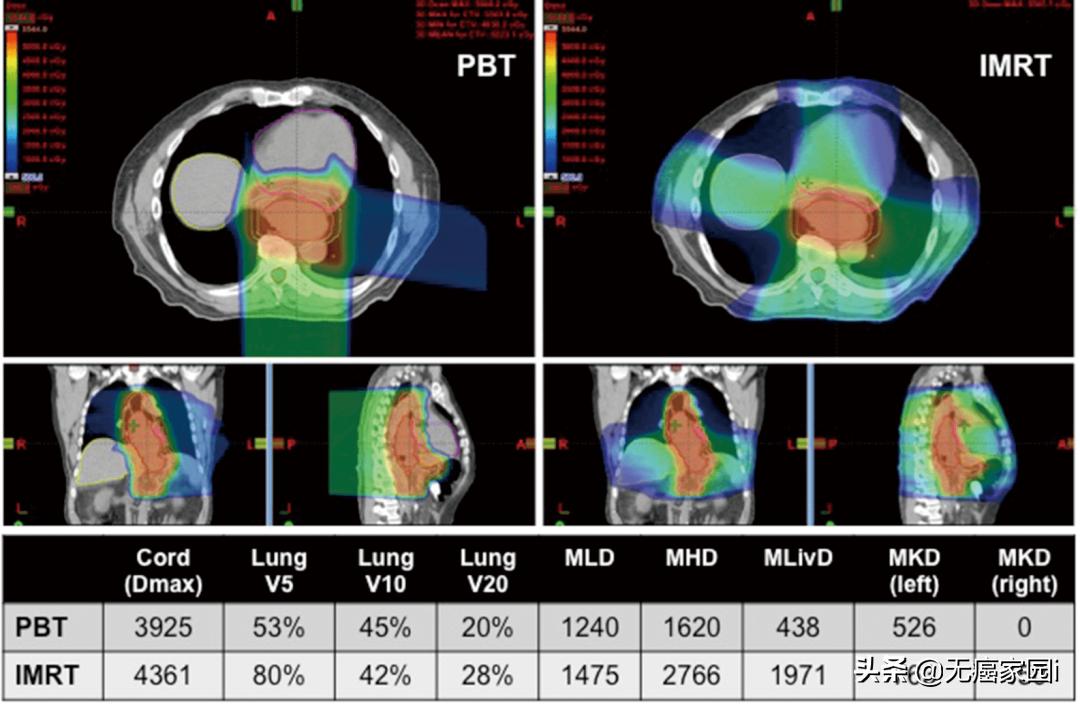

★据《胃肠肿瘤学》杂志刊登的一篇关于各项放疗技术治疗食管癌患者的剂量优势的文章显示,与3D适形放疗(3DCRT)相比,IMRT改善了器官的剂量分布;治疗计划和剂量学的比较研究进一步显示,与3DCRT和IMRT相比, 质子治疗可显著降低心脏和肺的照射剂量。质子治疗可最大程度地保护心脏前部组织,减少心脏的照射剂量,具有明显的临床优势。

图为质子治疗与IMRT治疗食管癌的剂量学比较,左为质子治疗,右为调强放疗

(注:Dmax,最大点剂量;Vx,体积乘以Gy的x剂量;MLD,平均肺部剂量;MHD,平均心脏剂量;MLivD,平均肝脏剂量;MKD,平均肾脏剂量)